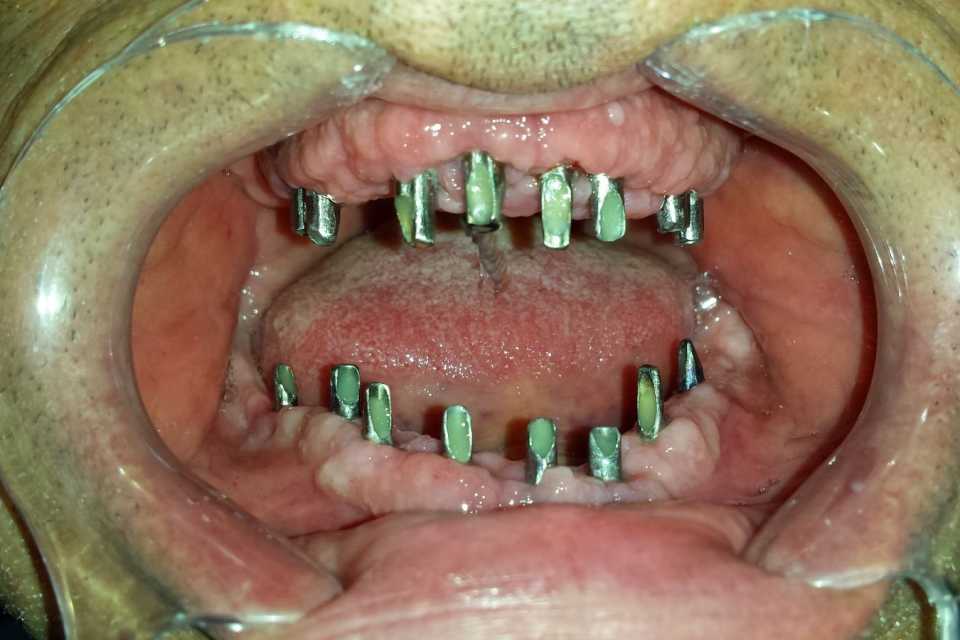

Pacientul s-a prezentat în cabinet cu o edentație totală bimaxilară. Au fost inserate 8 implanturi la maxilar și 8 implanturi la mandibulă. După perioada de osteointegrare au fost făcute două punți totale metalo-ceramice (ceramica Ivoclar D'sign).